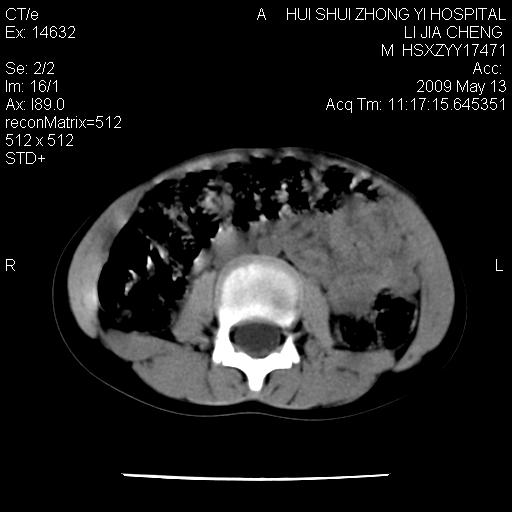

标题: PED1887:男性,6岁。反复脐周疼痛2年余。请各位老师看下腹 [打印本页]

标题: PED1887:男性,6岁。反复脐周疼痛2年余。请各位老师看下腹

该患者可自行好转,大小便未见异常,化验:便未见虫卵,血常规:wbc:8000;淋巴3600,中性45%

脂肪肉瘤可能性大,大血管边界不清,特别是腔静脉。不除外其他腹膜后肿瘤。

是不是有蛔虫哦,楼主图示块影前方肠管壁显著增厚,不除外慢性肠炎或肠壁占位,建议肠道准备后复查

肠道准备不足,im15---------------------18左侧腹腔病变?

肠管管壁均匀增厚,炎性可能

是小肠,壁稍厚可能是肠腔未很好充盈所致,腹部ct扫描未见明显异常。